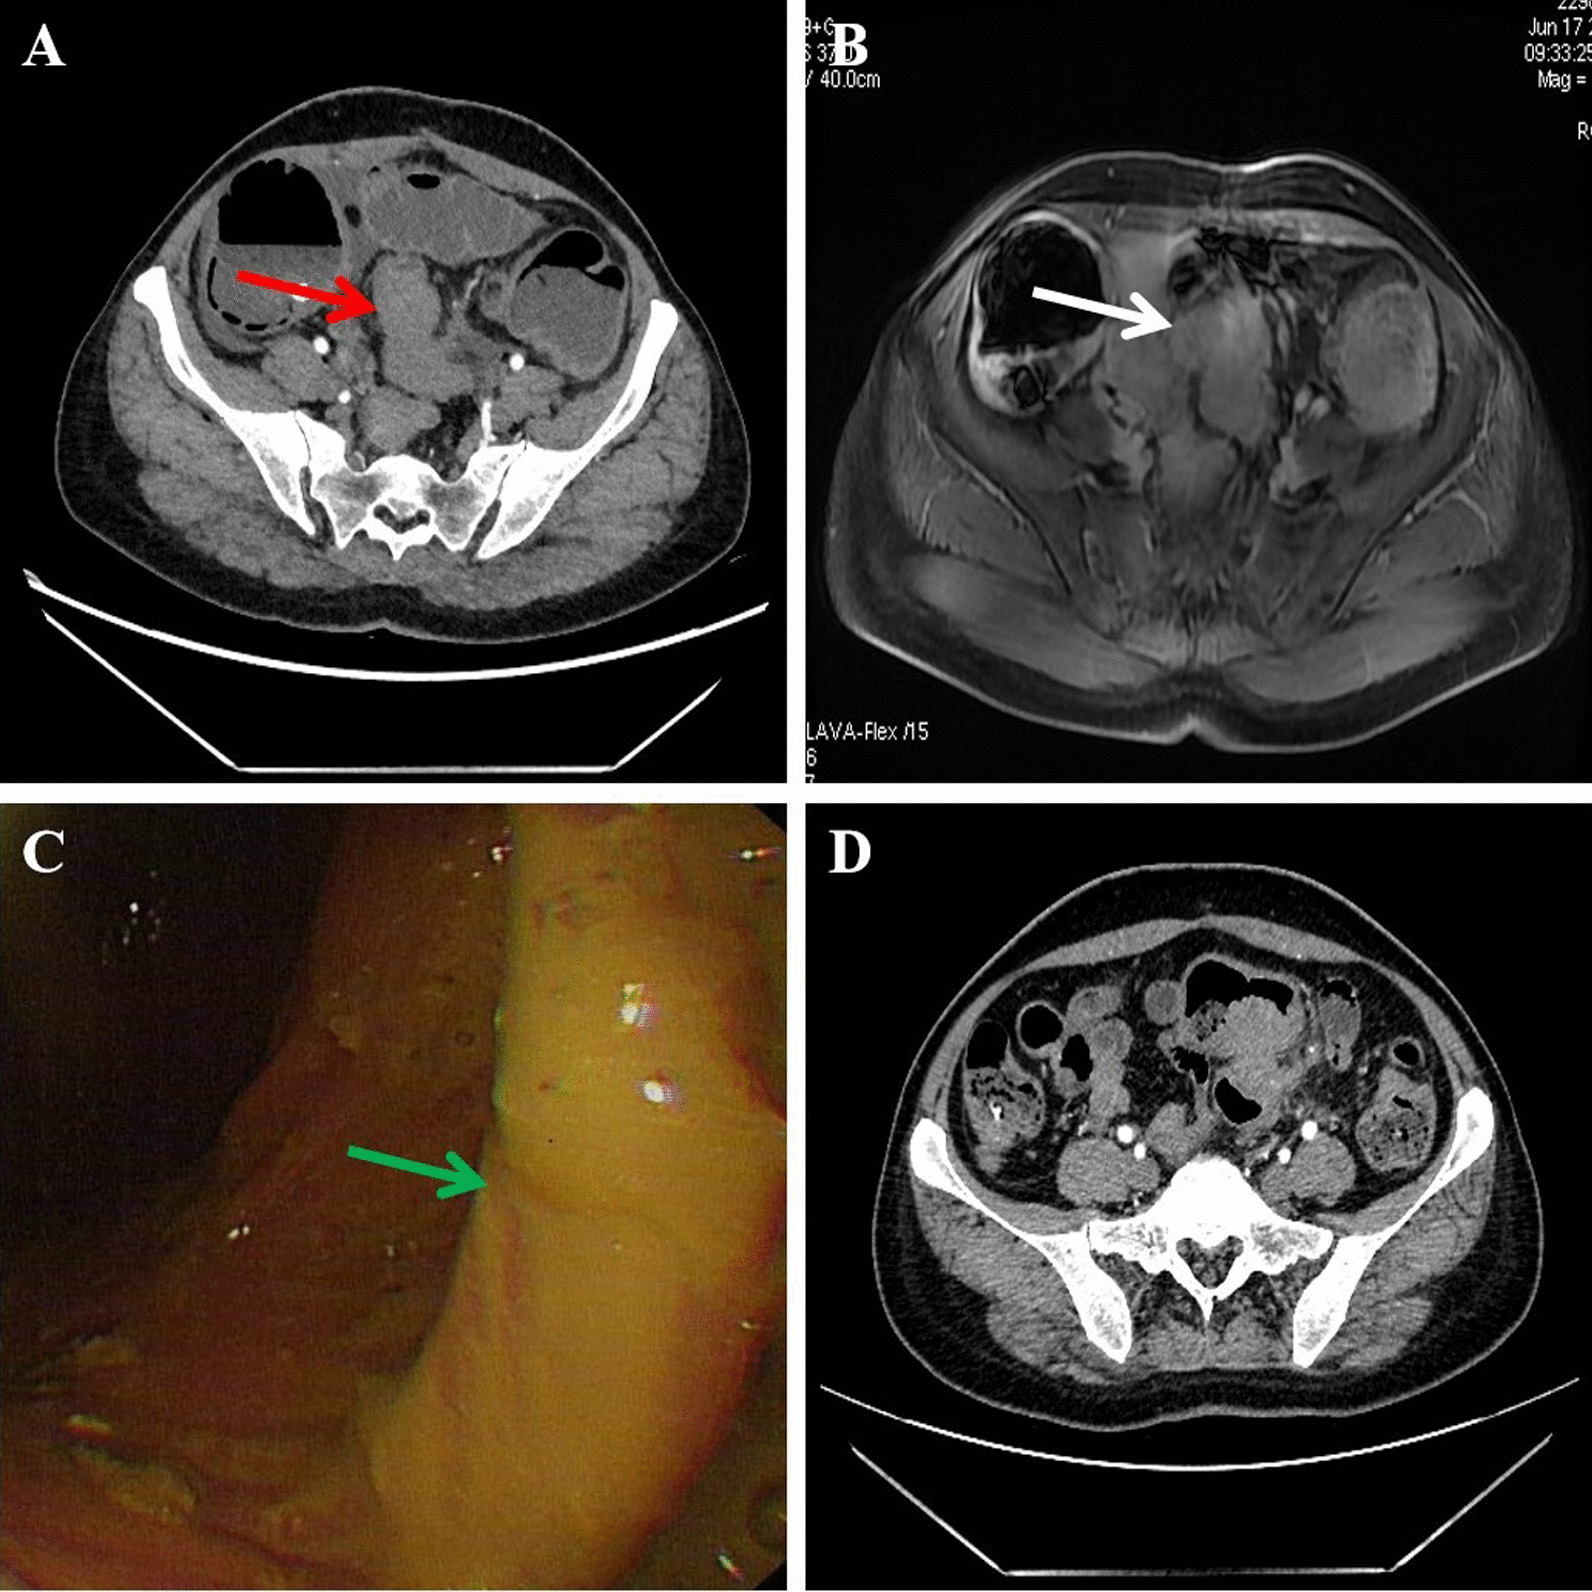

A 47-year-old woman, gravid 3 para 1, visited our hospital with complaints of abdominal pain and distension for 5 days. She was suffered with constipation accompanied by defecation for more than 1 year, menstrual exacerbation, no blood stool and fever, the menstrual cycle was also stably. She had a history of cesarean section 25 years ago and hysteromyoma excision 20 years ago. Physical examination only show left lower abdomen tenderness without peritoneal irritation. Digital rectal examination revealed no abnormalities. Her cancer antigen 125 level was 60.62 U/ml. Abdominal computed tomography (CT) revealed wall thickening from the upper rectum to sigmoid, secondary low intestinal obstruction and multiple myoma in the uterus (Fig. 1A). Colonoscopy showed a stenosing tumor formation in the upper rectum, but the mucous membrane is smooth (Fig. 1B). Biopsies only found nonspecific inflammation. Magnetic resonance imaging (MRI) also revealed neoplastic lesions of the sigmoid and rectum (Fig. 1C).

Fig. 1.

Preoperative examination of the patient. A Computed tomography (CT) revealed wall thickening from the upper rectum to sigmoid, accompanied by low intestinal obstruction (red arrow). B Magnetic resonance imaging (MRI) revealed neoplastic lesions of the sigmoid colon (white arrow). C Colonoscopy showed stenosing tumor formation in the upper rectum, the mucosal surface is smooth (green arrow). D After 7 days of colon decompression, computed tomography reexamination showed the dilatation of the colon was significantly less than before

A primary diagnosis of intestinal obstruction secondary to rectal endometriosis was made according to the laboratory and instrument examinations. After 7 days of colon decompression and nutrition support therapy, the patient's abdominal distension was significantly relieved, CT reexamination showed that the dilatation of the colon was significantly less than before (Fig. 1D). An operation of laparoscopic partial rectal and sigmoid colon resection and total hysterectomy was performed successfully. The specimen was removed through a small abdominal incision (about 5 cm). During the operation, we found a stenosis recto-sigmoid mass and multiple adenomyoma of the uterus. The mass had adhesion with the posterior lamina of right broad ligament and the posterior uterine wall, without infiltration into the rectovaginal septum (Fig. 2).